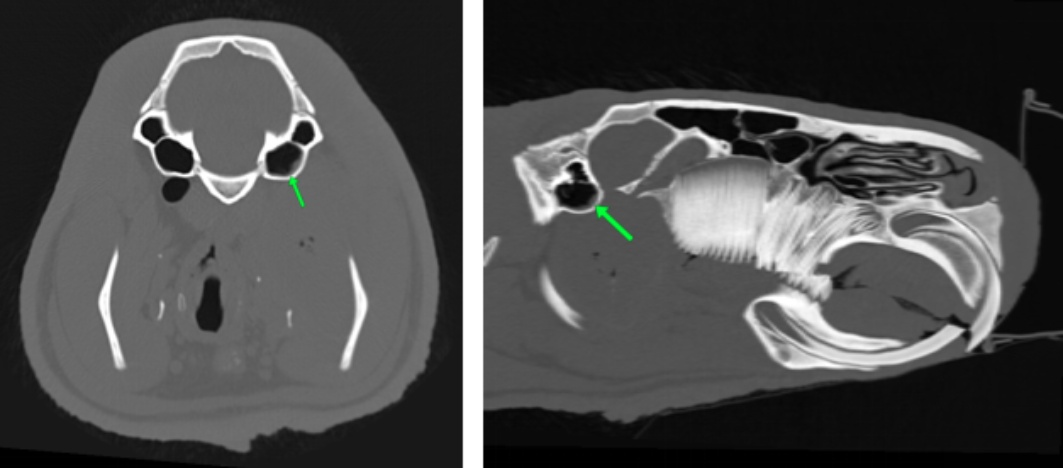

使用万东医疗的OpenCT机,将患病水豚以背卧位及侧卧位保定进行头部平扫和三维成像,影像结果见图1图2

图1(A)可知,其右侧喉咽部会厌水平处有一细棒状金属密度异物影,长度约1.8 cm,周围软组织密度降低,软组织内有多个小气泡影。由图1(B)可知其双侧颞下颌关节未有明显脱位。由图1(C)可知,其右侧鼓室重力侧有层状中等密度影,左侧鼓室内充满气体影,外耳道通畅,耳道壁有点状钙化灶。各牙齿密度正常,齿根处无明显骨质溶解,未有齿根过长,双侧切齿对合良好。脑中线居中,脑实质无明显异常密度影。鼻中隔居中,筛骨完整、对称,鼻腔内无明显渗出影。

Figure 1. CT image of diseased capybara

1. 患病水豚CT影像